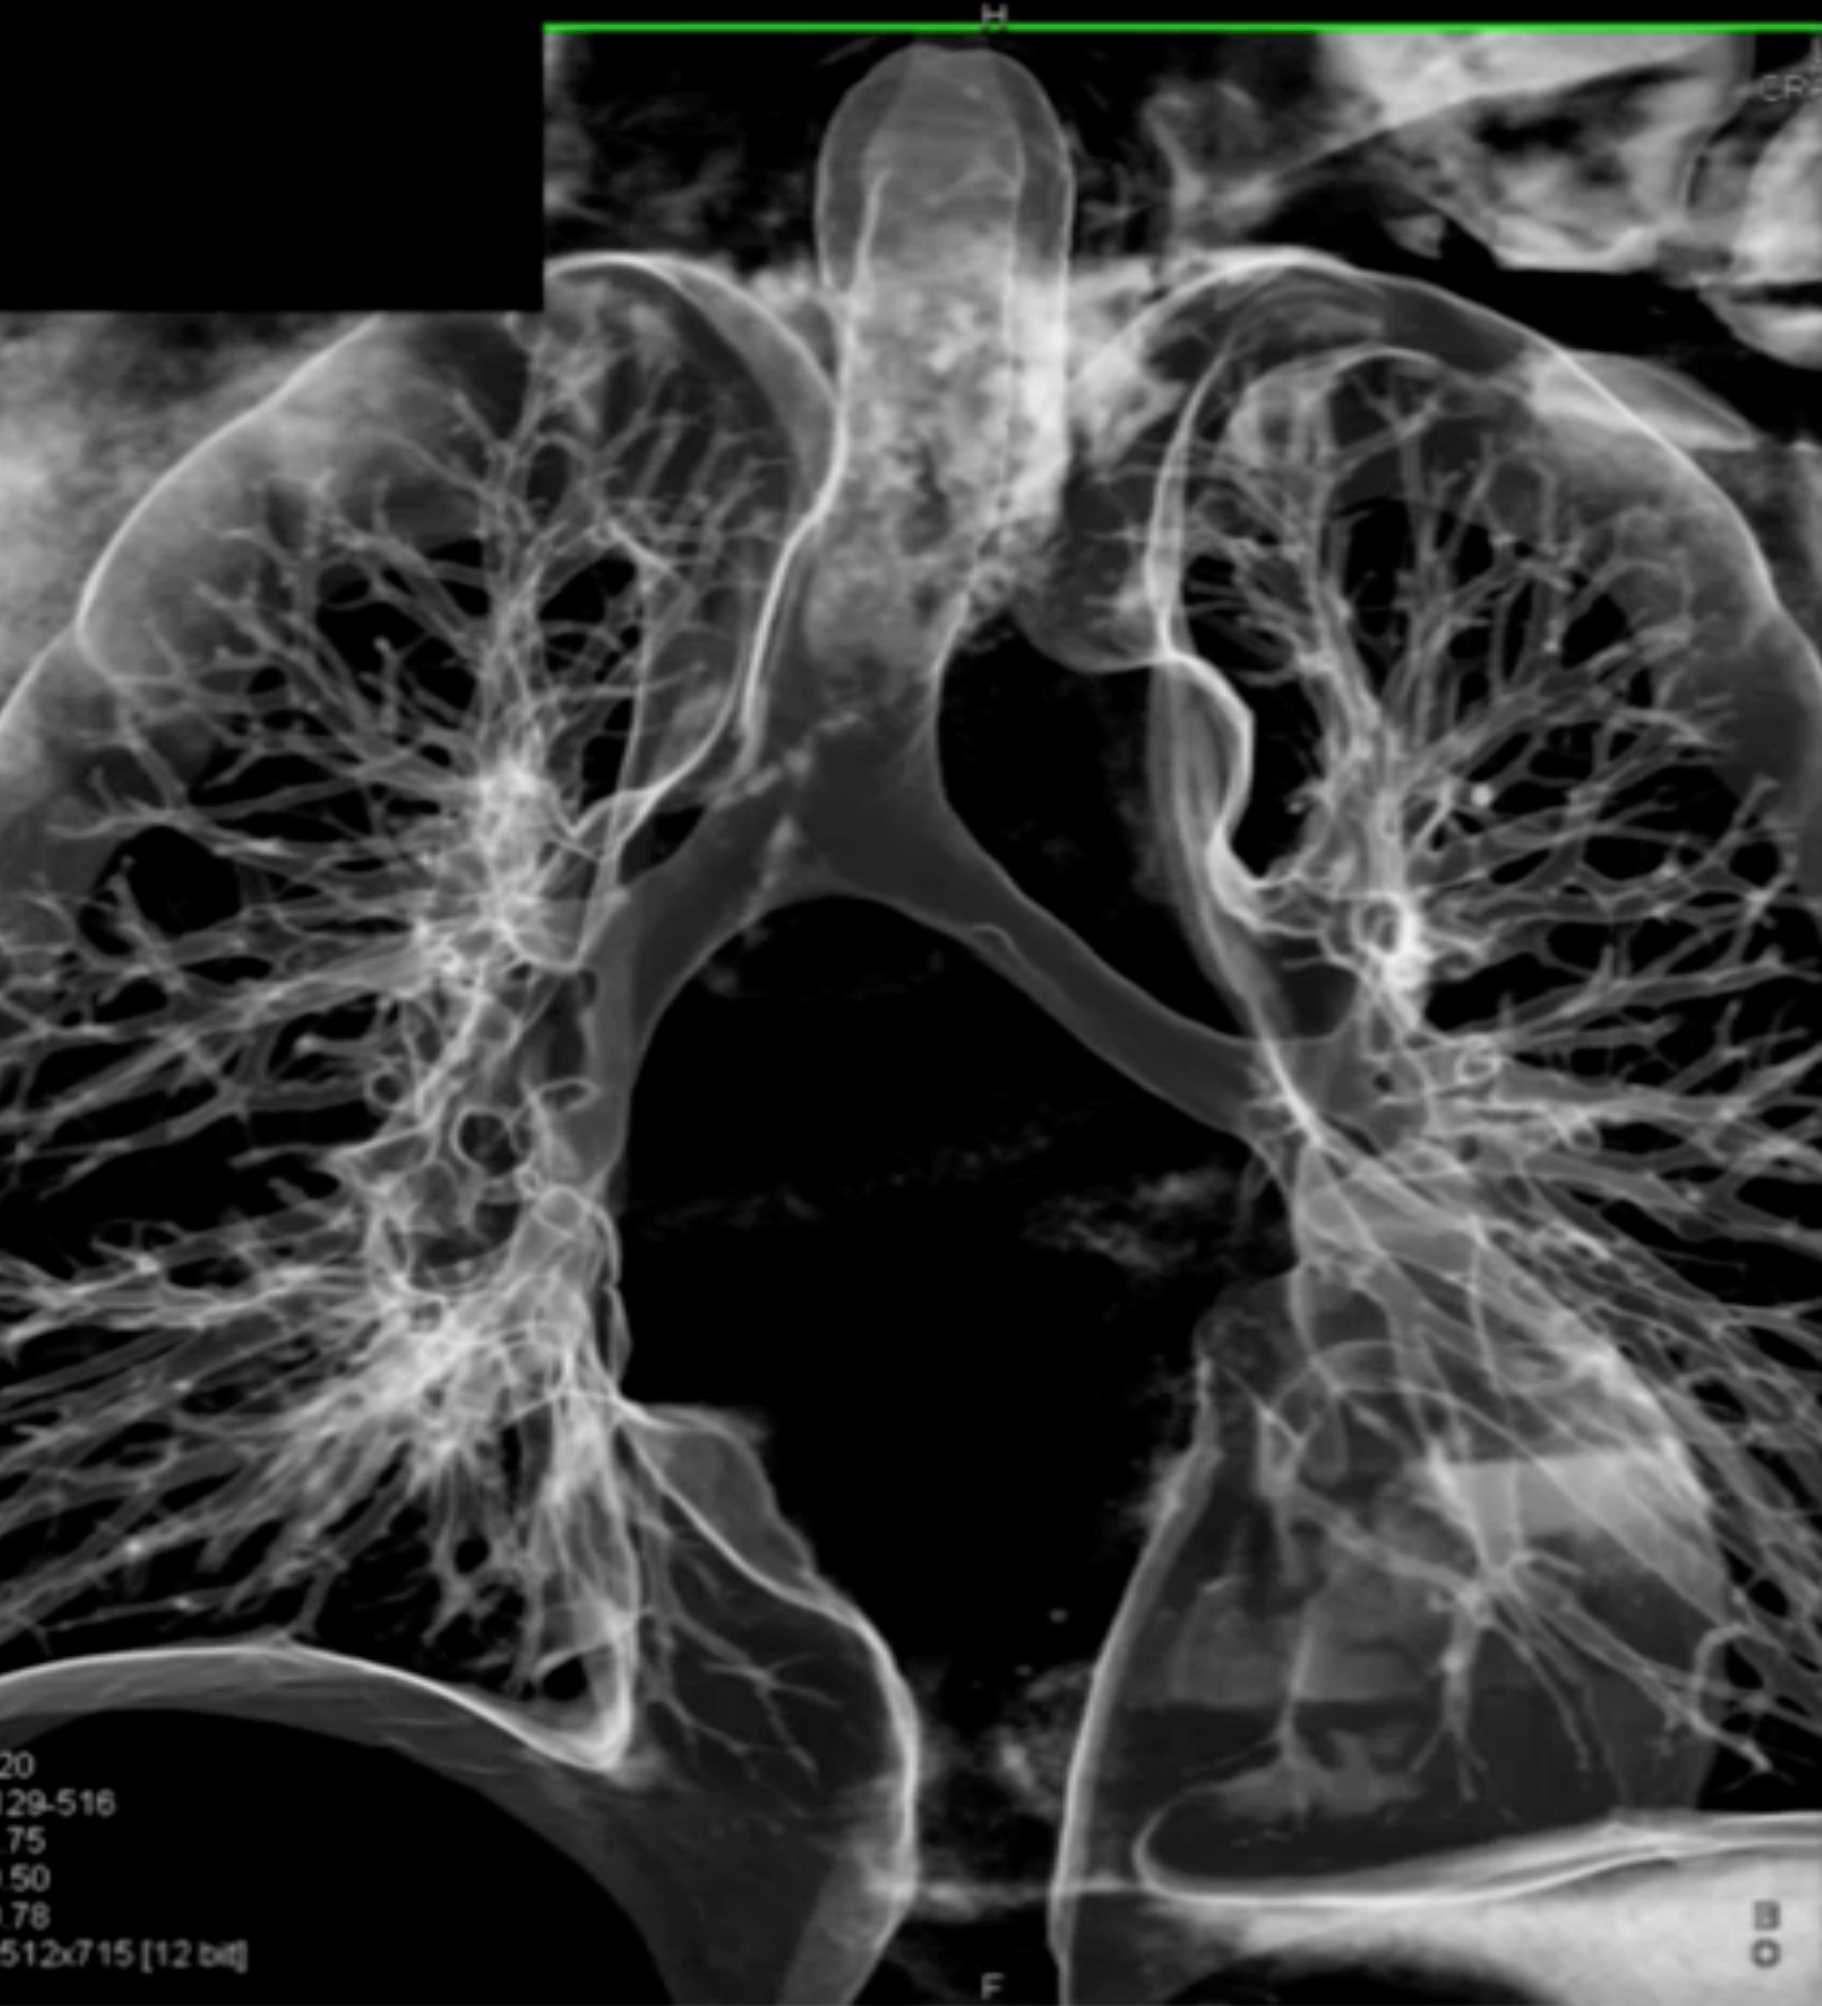

Fibrosing Mediastinitis